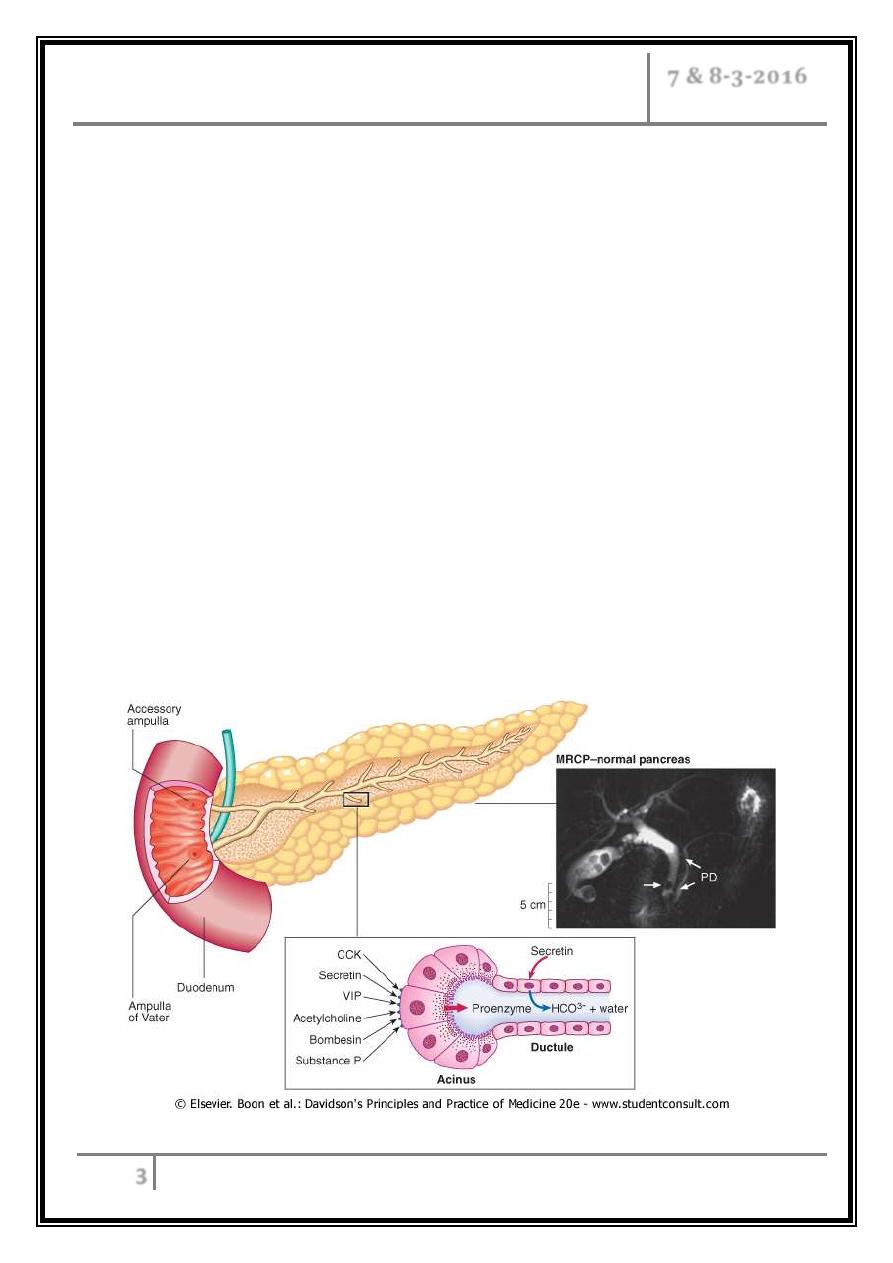

Pancreatic structure and function

Diagram showing stimulus-secretion coupling of pancreatic cell protein

secretion. There is no CCK receptor in humans; stimulation is probably

via neural fibres. VIP, vasoactive intestinal polypeptide; CCK,

cholecystokinin; ACh, acetylcholine